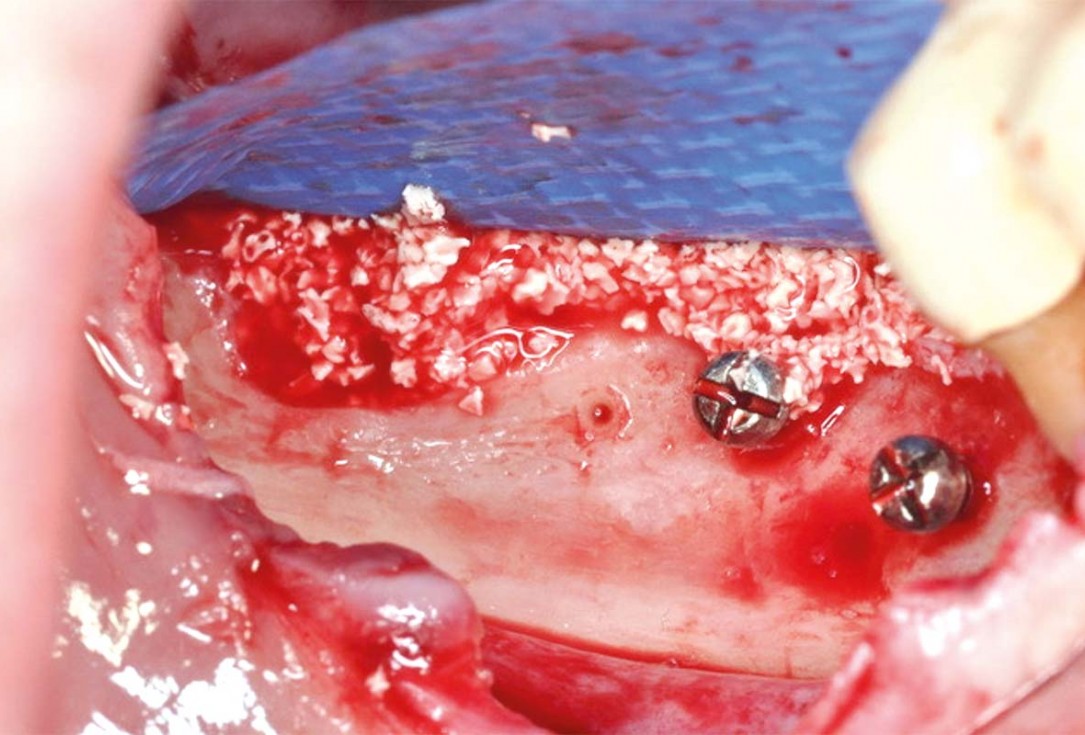

03/10 - Placement of tenting screws and bone augmentation on the lateral aspect with cerabone® mixed with autologous bone chips. permamem® in place for covering.

Vertical and horizontal GBR using permamem®, cerabone® and autologous bone - Dr. D. B. Hangyasi